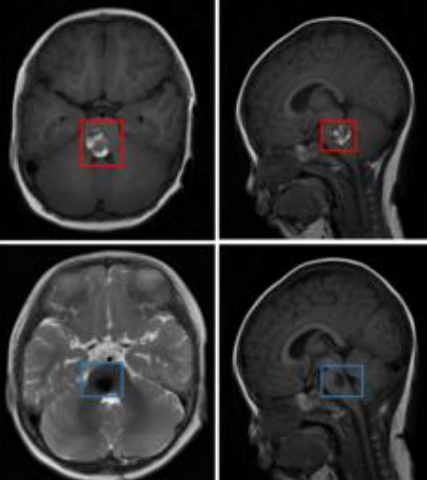

海绵状脑血管瘤是指有众多薄壁血管组成的海绵状异常血管团,即畸形血管团,虽然带了一个“瘤”字,但并不是的肿瘤,看起来有点像爆米花。既然不是肿瘤,那么脑干海绵状血管瘤还严重吗?

脑干海绵状血管瘤严重吗?INC国际神经外科医生集团旗下组织国际神经外科顾问团成员巴特朗菲教授指出,海绵状血管瘤是比较严重的疾病,因为海绵状血管瘤是一团血管,类似于海绵状,到处都是孔洞,不利于血流的稳定性。在某些诱发因素的情况下,比如外伤、高血压、情绪激动等等情况,有可能出现破裂出血的情况。

海绵纸血管瘤会破裂出血,所以位于脑干位置的脑干海绵状血管瘤是严重的。这是因为脑干是中枢神经系统较重要的生理功能区之一,脑干维持人体的生命,包括心跳、呼吸、消化等重要生理功能。而海绵纸血管瘤会使脑干不断受到压迫,导致出血,如果是轻微的,及时采取措施和治疗还好,若是出现大面积的脑出血,有可能会造成颅内压升高,引起脑疝,就会造成患者的呼吸循环停止,造成死亡,出血多次甚至可能导致直接当场死亡,国内外因脑出血直接死亡的报道不在少数。所以,脑干海绵状血管瘤是很严重的疾病,要及早的发现,并且及早进行相应治疗。